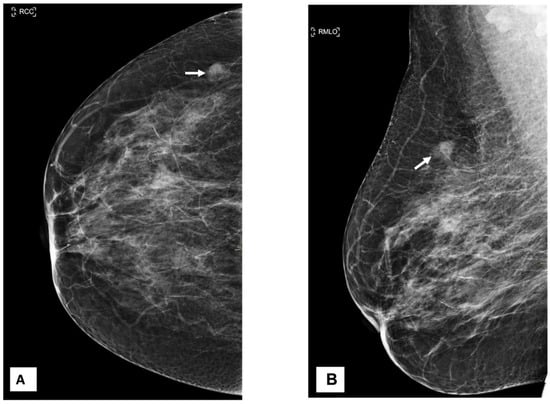

A 54-year-old woman came to our facility for the screening procedure. A mammogram was performed on her. The patient had no remarkable medical or family history, and she was here for routine screening. Mammography showed focal asymmetry of equal density in the upper-outer quadrant of the right breast, which was 9 cm distant from the nipple. The focal asymmetry was 1 cm in size. This finding partially persisted in the additional targeted compression view (Figure 1). The targeted ultrasound examination did not reveal any findings that were suitable for inclusion in the criteria. After an additional nine months had elapsed, a breast mass in the axillary region of the right breast was identified as being the source of her symptoms. During the clinical examination, it was discovered that the patient had a mass that was uncomfortable, moveable, and irregularly shaped and that measured 2 × 2 cm2.

There was no indication of inflammation or swelling in either breast. A mammogram showed a large fat-containing oval-shaped lump with a circumscribed outline, and the mass in the upper outer quadrant of the right breast was approximately 9 cm from the nipple and measured 3 × 3.5 cm2 (Figure 2). However, mammography of the left breast showed nothing out of the ordinary. The subsequently targeted ultrasonography (US) revealed a heterogeneous isoechoic irregularly shaped solid mass that measured 3.3 × 3 cm2 and had eccentric cystic foci placed at the 9 o’clock position and approximately 8 cm away from the nipple (Figure 3). Differential diagnoses include phyllode tumor (PT) in addition to liposarcoma. The patient sought treatment at a tertiary hospital, where she underwent a right breast biopsy, and based on the findings of that procedure, a right lumpectomy without an axillary dissection was conducted. When seen under a microscope, the tumor was found to contain mature adipocytes, atypical spindle cells, and multivacuolated lipoblasts. All of these cell types were discovered to be embedded in a loose myxoid to fibrous stroma within the tumor itself. This information is provided by the pathology report. In addition, there were a significant number of regions that had pleomorphic cells, multinucleated, weird, enormous cells, and lipoblasts (Figure 4 and Figure 5).

Figure 2. Craniocaudal and mediolateral oblique nine-month follow-up mammography of the right breast. (A,B) A large, circumscribed fat-containing oval-shaped lump approximately 9 cm from the nipple measuring 3 × 3.5 cm2 (arrows) with no associated suspicious features (suspicious microcalcification or architectural distortion).